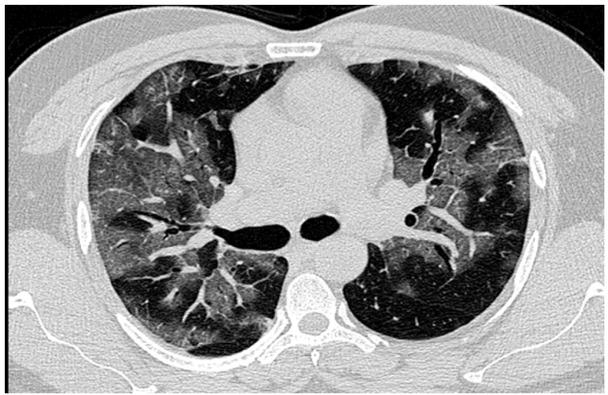

On admittance to the TCU, an initial examination indicated that he had extensive subcutaneous emphysema with bilateral crepitus. This diagnosis was not included in the referral letter from the private hospital and it may be assumed that such a diagnosis had not been previously made. The referral letter did state that he had had a contrast enhanced computed tomography (CECT) following a non-resolving pneumonia, the films of which had been enclosed with the letter. This indicated severe right to left pneumomediastinum with extensive subcutaneous emphysema accompanied by interstitial pneumonitis features (Fig. 1A). Initially, treatment for pneumonia was continued and throat and nasal swabs sent for laboratory examination. Both throat and nasal swab tested positive for the H1N1 pandemic 2009 strain.

An axial section of the high resolution computed tomography chest image in a lung window showing patchy diffuse ground glass density s/o acute interstitial pneumonia.